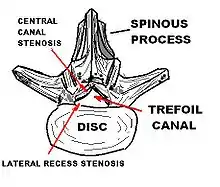

Spinal stenosis is an abnormal narrowing of the spinal canal or neural foramen that results in pressure on the spinal cord or nerve roots.[6] Symptoms may include pain, numbness, or weakness in the arms or legs.[1] Symptoms are typically gradual in onset and improve with leaning forward.[1] Severe symptoms may include loss of bladder control, loss of bowel control, or sexual dysfunction.[1]

Causes may include osteoarthritis, rheumatoid arthritis, spinal tumors, trauma, Paget's disease of the bone, scoliosis, spondylolisthesis, and the genetic condition achondroplasia.[3] It can be classified by the part of the spine affected into cervical, thoracic, and lumbar stenosis.[2] Lumbar stenosis is the most common, followed by cervical stenosis.[2] Diagnosis is generally based on symptoms and medical imaging.[4]

In lumbar stenosis, the spinal nerve roots in the lower back are compressed which can lead to symptoms of sciatica (tingling, weakness, or numbness that radiates from the low back and into the buttocks and legs).

Cervical spinal stenosis can be far more dangerous by compressing the spinal cord. Cervical canal stenosis may lead to myelopathy, a serious condition causing symptoms including major body weakness and paralysis.[14] Such severe spinal stenosis symptoms are virtually absent in lumbar stenosis, however, as the spinal cord terminates at the top end of the adult lumbar spine, with only nerve roots (cauda equina) continuing further down.[15] Cervical spinal stenosis is a condition involving narrowing of the spinal canal at the level of the neck. It is frequently due to chronic degeneration,[16] but may also be congenital or traumatic. Treatment frequently is surgical.[16]

The diagnosis of spinal stenosis involves a complete evaluation of the spine. The process usually begins with a medical history and physical examination. X-ray and MRI scans are typically used to determine the extent and location of the nerve compression.

Myelography